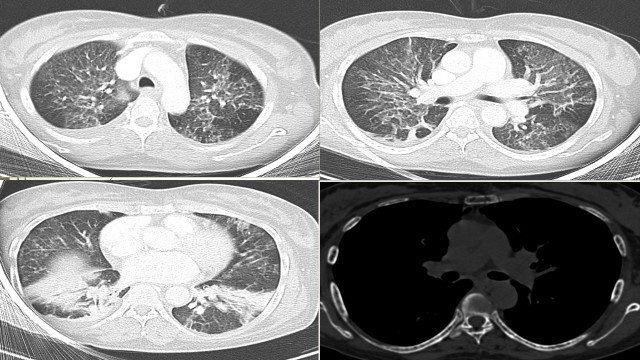

During the course, despite the ongoing treatment, she developed recurrent junctional tachycardia and worsening of respiration due to ILD. Chest X-ray showed bilateral lung infiltrates. CT chest showed patchy ground glass opacification with interlobular septal thickening in bilateral peri-hilar lung parenchyma with multiple osteolytic lesions in vertebrae and sternum [figure 1].

CT chest showed significant improvement [figure 7].